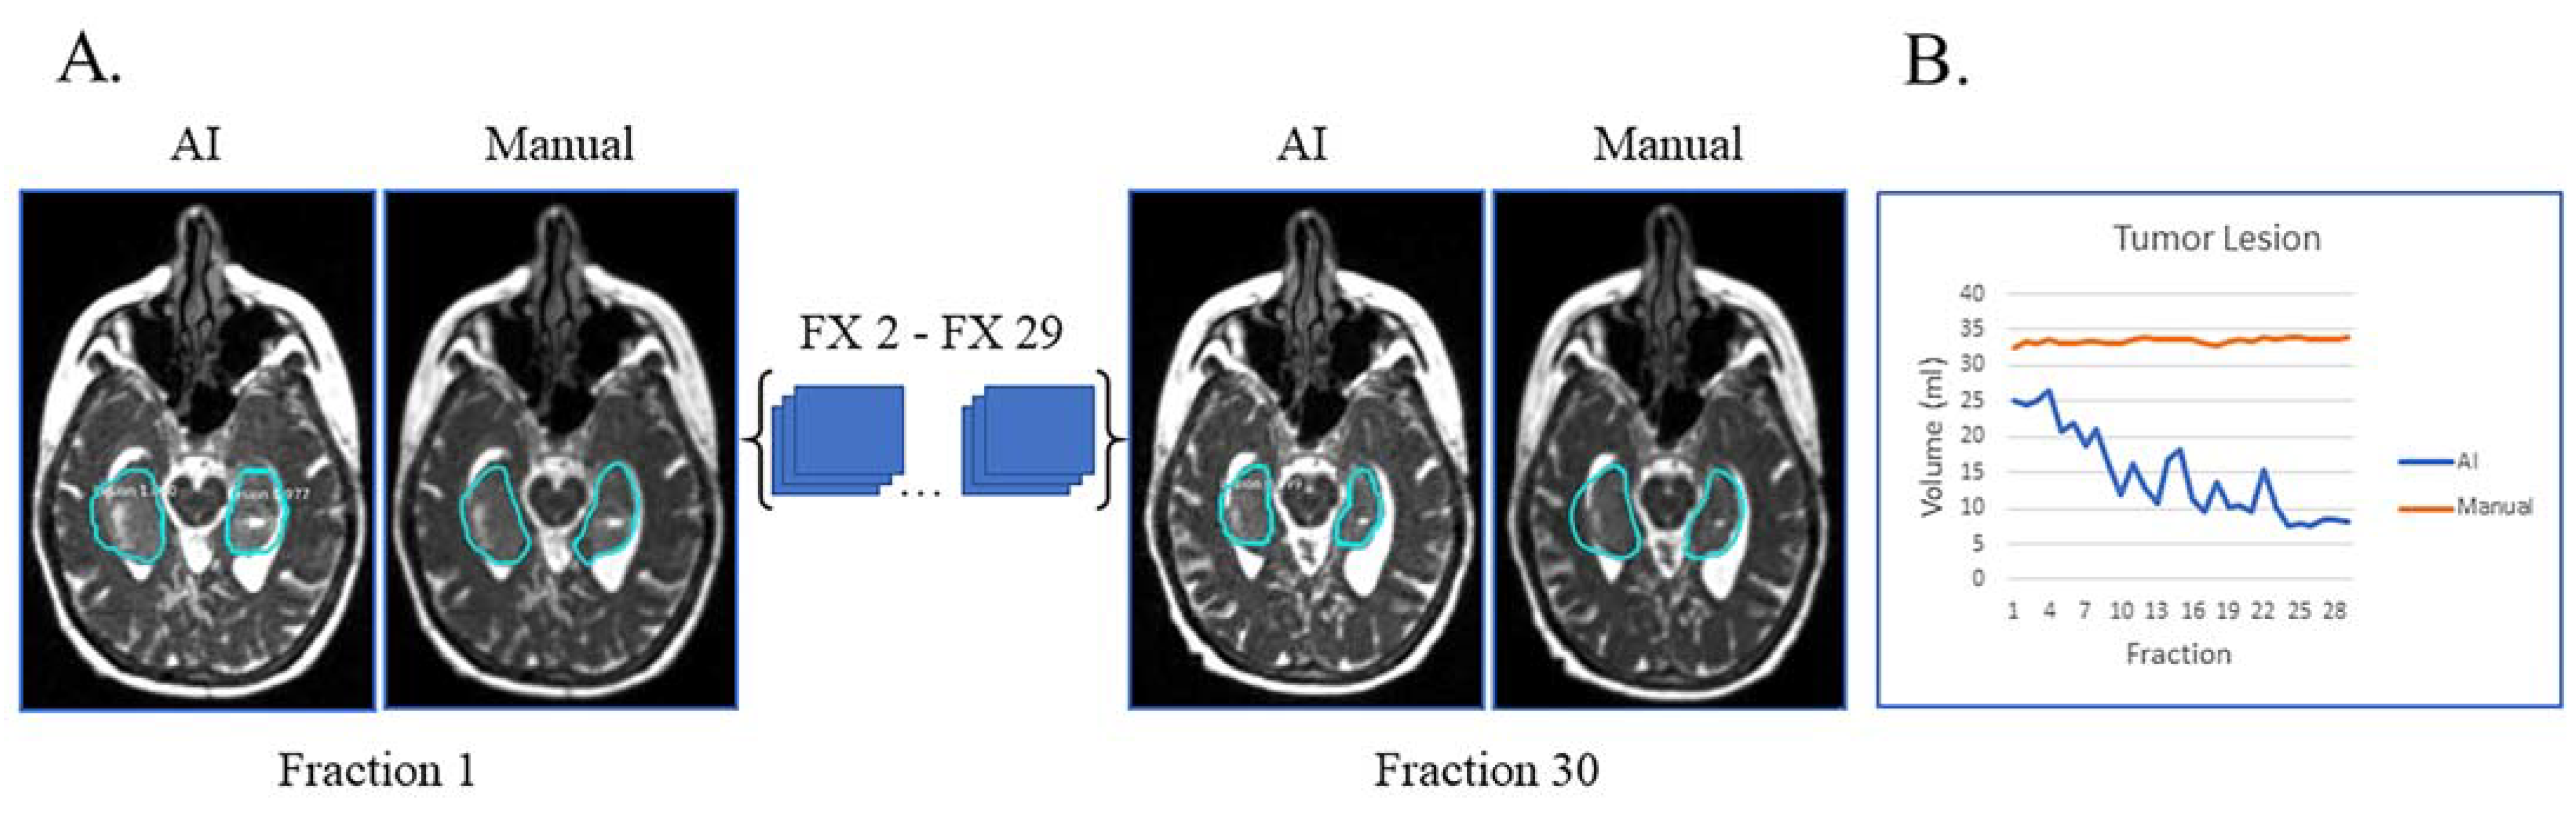

In Figure 3A, the patient had tumor lesion only following a biopsy. This is an example of a case where the AI volumes deviate from the manual volumes: the trajectory from the manual contours shows little to no volume change during treatment while the AI contours show a decreasing volume trend (Figure 3B). On re-review of this subject’s imaging, there is subtle visual tumor lesion shrinkage over time, consistent with the AI contours. This case points out that there can be errors in manual contours, in particular when reviewing small daily or weekly changes. In this subject’s case, it is fair to say that the network performed a superior job to the manual contours.

Figure 3.

Biopsy only with tumor lesion without progression during RT and no progression on post-treatment MRI. (A) Auto-segmentation (left) and manual (right) contours of tumor lesion (cyan) at the first and last treatment fractions (FX) shown on MRI-linac bSSFP. (B) Volumes derived from AI (blue) and manual segmentation (orange) across treatment fractions demonstrate subtle shrinkage not appreciated by manual contouring but apparent in retrospect.